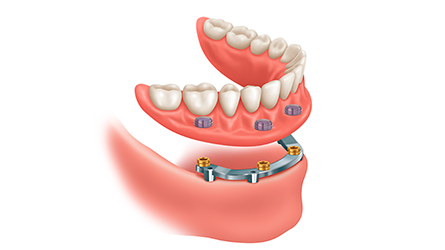

Dental Implant Supported Dentures

Dental Implants Offered by Our Hamilton Dental Implant Specialists: